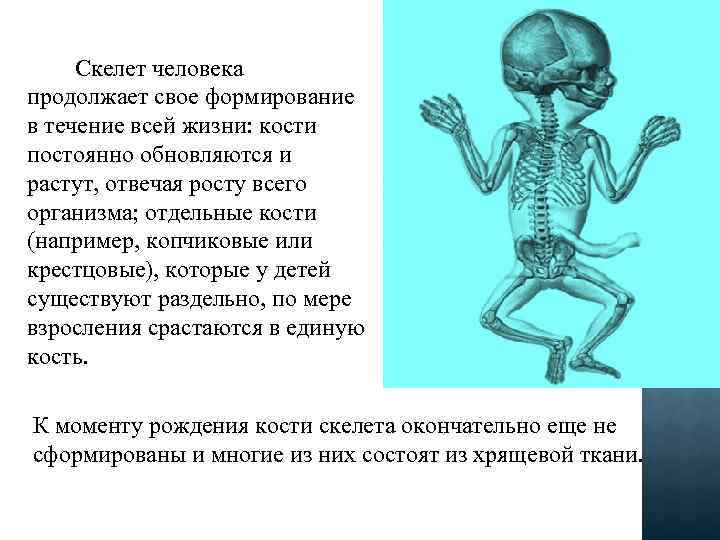

Скелет человека продолжает свое формирование в течение всей жизни: кости постоянно обновляются и растут, отвечая росту всего организма; отдельные кости (например, копчиковые или крестцовые), которые у детей существуют раздельно, по мере взросления срастаются в единую кость. К моменту рождения кости скелета окончательно еще не сформированы и многие из них состоят из хрящевой ткани.